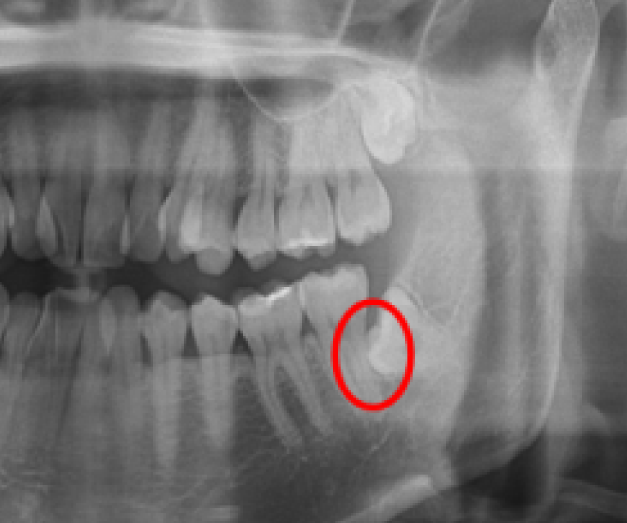

問診とレントゲン撮影:全身疾患やアレルギー、常用している薬などの確認を行います。また、レントゲン撮影を行い、親知らずの位置や角度、周囲の神経や血管の位置を確認します。

◆横向きに生えている親知らず:歯を砕きながら抜歯する必要があります。抜歯時間は約30分です。

◆骨の中に潜っている親知らず:被っている歯茎や骨を取り除き、親知らずを砕いて抜歯する必要があります。抜歯時間は約5分です。